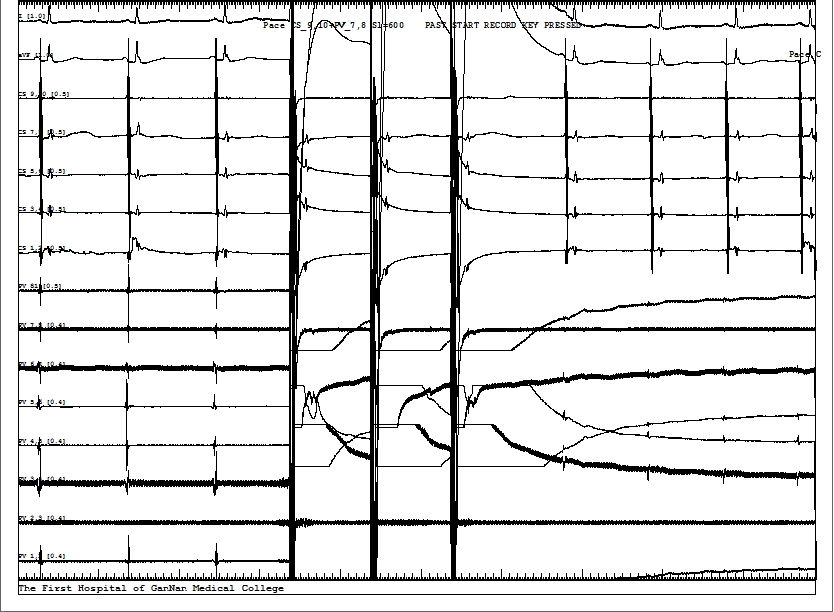

使用鑫律通科技研发的篮状多路脉冲电场消融系统,手术团队先后为两名患者顺利成功实施了阵发性房颤的脉冲电场导管消融手术。该技术把环肺标测功能融合到脉冲电场消融导管中,在X光造影和多导仪指导下(见图2,不用额外的环肺标测导管或三维标测系统),一次放电后肺静脉电位消失(图3是典型的一次性(One-shot)隔离肺静脉的心电图),起搏验证传导阻滞成功(见图4)。为了确保PFA的长期有效性,术者多次放电巩固,该肺静脉的总放电时间仅为2.88秒,四个肺静脉的总放电时间为13.68秒,用时仅约1个小时,本PFA系统快速完成首例阵发性房颤治疗。随后对另一位患者也成功进行了PFA治疗房颤的手术,5个肺静脉(两个右上肺静脉)的总放电时间是16.56秒,每个肺静脉的平均放电时间为3.31秒。美国波士顿科学的FaraPulse产品的每个肺静脉放电时间为20秒,本产品的放电时间仅为波科产品的17%,缩短了83%。其他国内外PFA产品的每个肺静脉的放电时间可能更长,加上多次消融之间的导管位置调整,每个肺静脉的总时间相差达数分钟,本产品四个肺静脉的总时间会节约至少10分钟,也就是节约至少40%以上。

图3. 肺静脉(PV)PFA消融过程心电图(上图中下面8路PV心电图来自PFA消融导管)